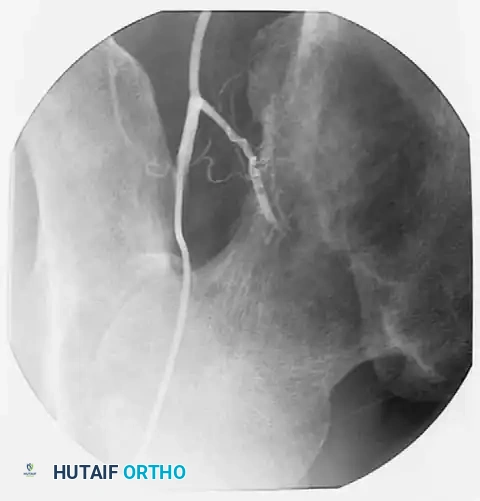

Preoperative Optimization and Embolization

Highly cellular marrow-replacing tumors (including lymphoma, myeloma, and renal/thyroid metastases) can be massively vascular. If open reduction or extensive exposure is anticipated, preoperative angiography and embolization should be strongly considered to mitigate catastrophic intraoperative hemorrhage.

Post-embolization angiogram showing successful occlusion of the tumor's feeding vessels. This critical step minimizes intraoperative blood loss, which can otherwise be extensive and life-threatening.